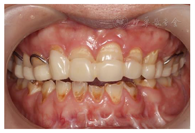

(1)面部检查:面部外形不对称,颏部居中,两侧口角高度不一致,面下1/3高度减小,两侧颧弓突度一致,下颌前突。中位笑线,上唇长度适中(图1)。(2)关节检查:颞颌关节:弹响(-),杂音(-),疼痛(-)。开口度正常,开口型有偏斜,肌肉触诊压痛:右侧上颌结节(+)、左侧上颌结节(++)、双侧翼内肌(+),其他肌肉及颞下颌关节区未诉异常,关节载荷实验无任何紧张和疼痛不适。(3)口内检查:上下颌牙中线较面中线向右偏斜,前后牙广泛不均匀磨耗,前牙磨耗后呈刃状;14、21、22、23及下颌牙唇颊侧颈部见釉质缺损,部分牙本质暴露,呈黄褐色,少量白垩色;44牙见开髓孔,表面暂封。12缺失,缺失牙间隙无。全口牙龈色形质未见异常,11牙、21牙唇侧牙龈龈缘高度不一致,21牙较11牙龈缘高约3mm。全口口腔卫生状况良好,菌斑、软垢少量,未及牙石及牙周袋。咬合检查:11-14牙与对颌牙反

,21牙与31、31牙对刃,左侧尖牙至前磨牙深覆盖,

曲线不平(图2,图3)。(4)影像学检查: